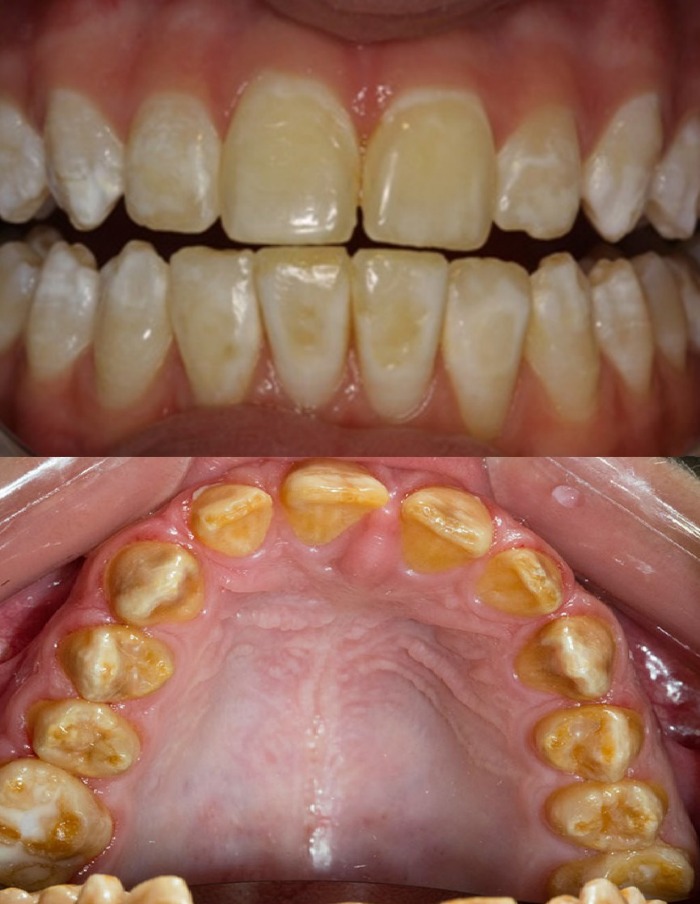

(Слева) На фотографии видна тонкая шероховатая поверхность остатков эмали коричневого цвета у пациента с гипоминерализационным несовершенным амелогенезом. Обратите внимание на передний открытый прикус.

(Справа) На кадрированной панорамной рентгенограмме визуализируется эмаль такой же рентгеновской плотности, как и подлежащий дентин, что характерно для гипоминерализационного и гипоматурационного типов. Зубы выглядят заостренными, проксимальные контакты отсутствуют.

• Гипоминерализационный тип:

о Зубы обычной формы с желтовато-оранжевой эмалью, окрашивающейся затем в коричневый цвет

о Эмаль мягкая и легко стирается

о Быстро возникает зубной камень